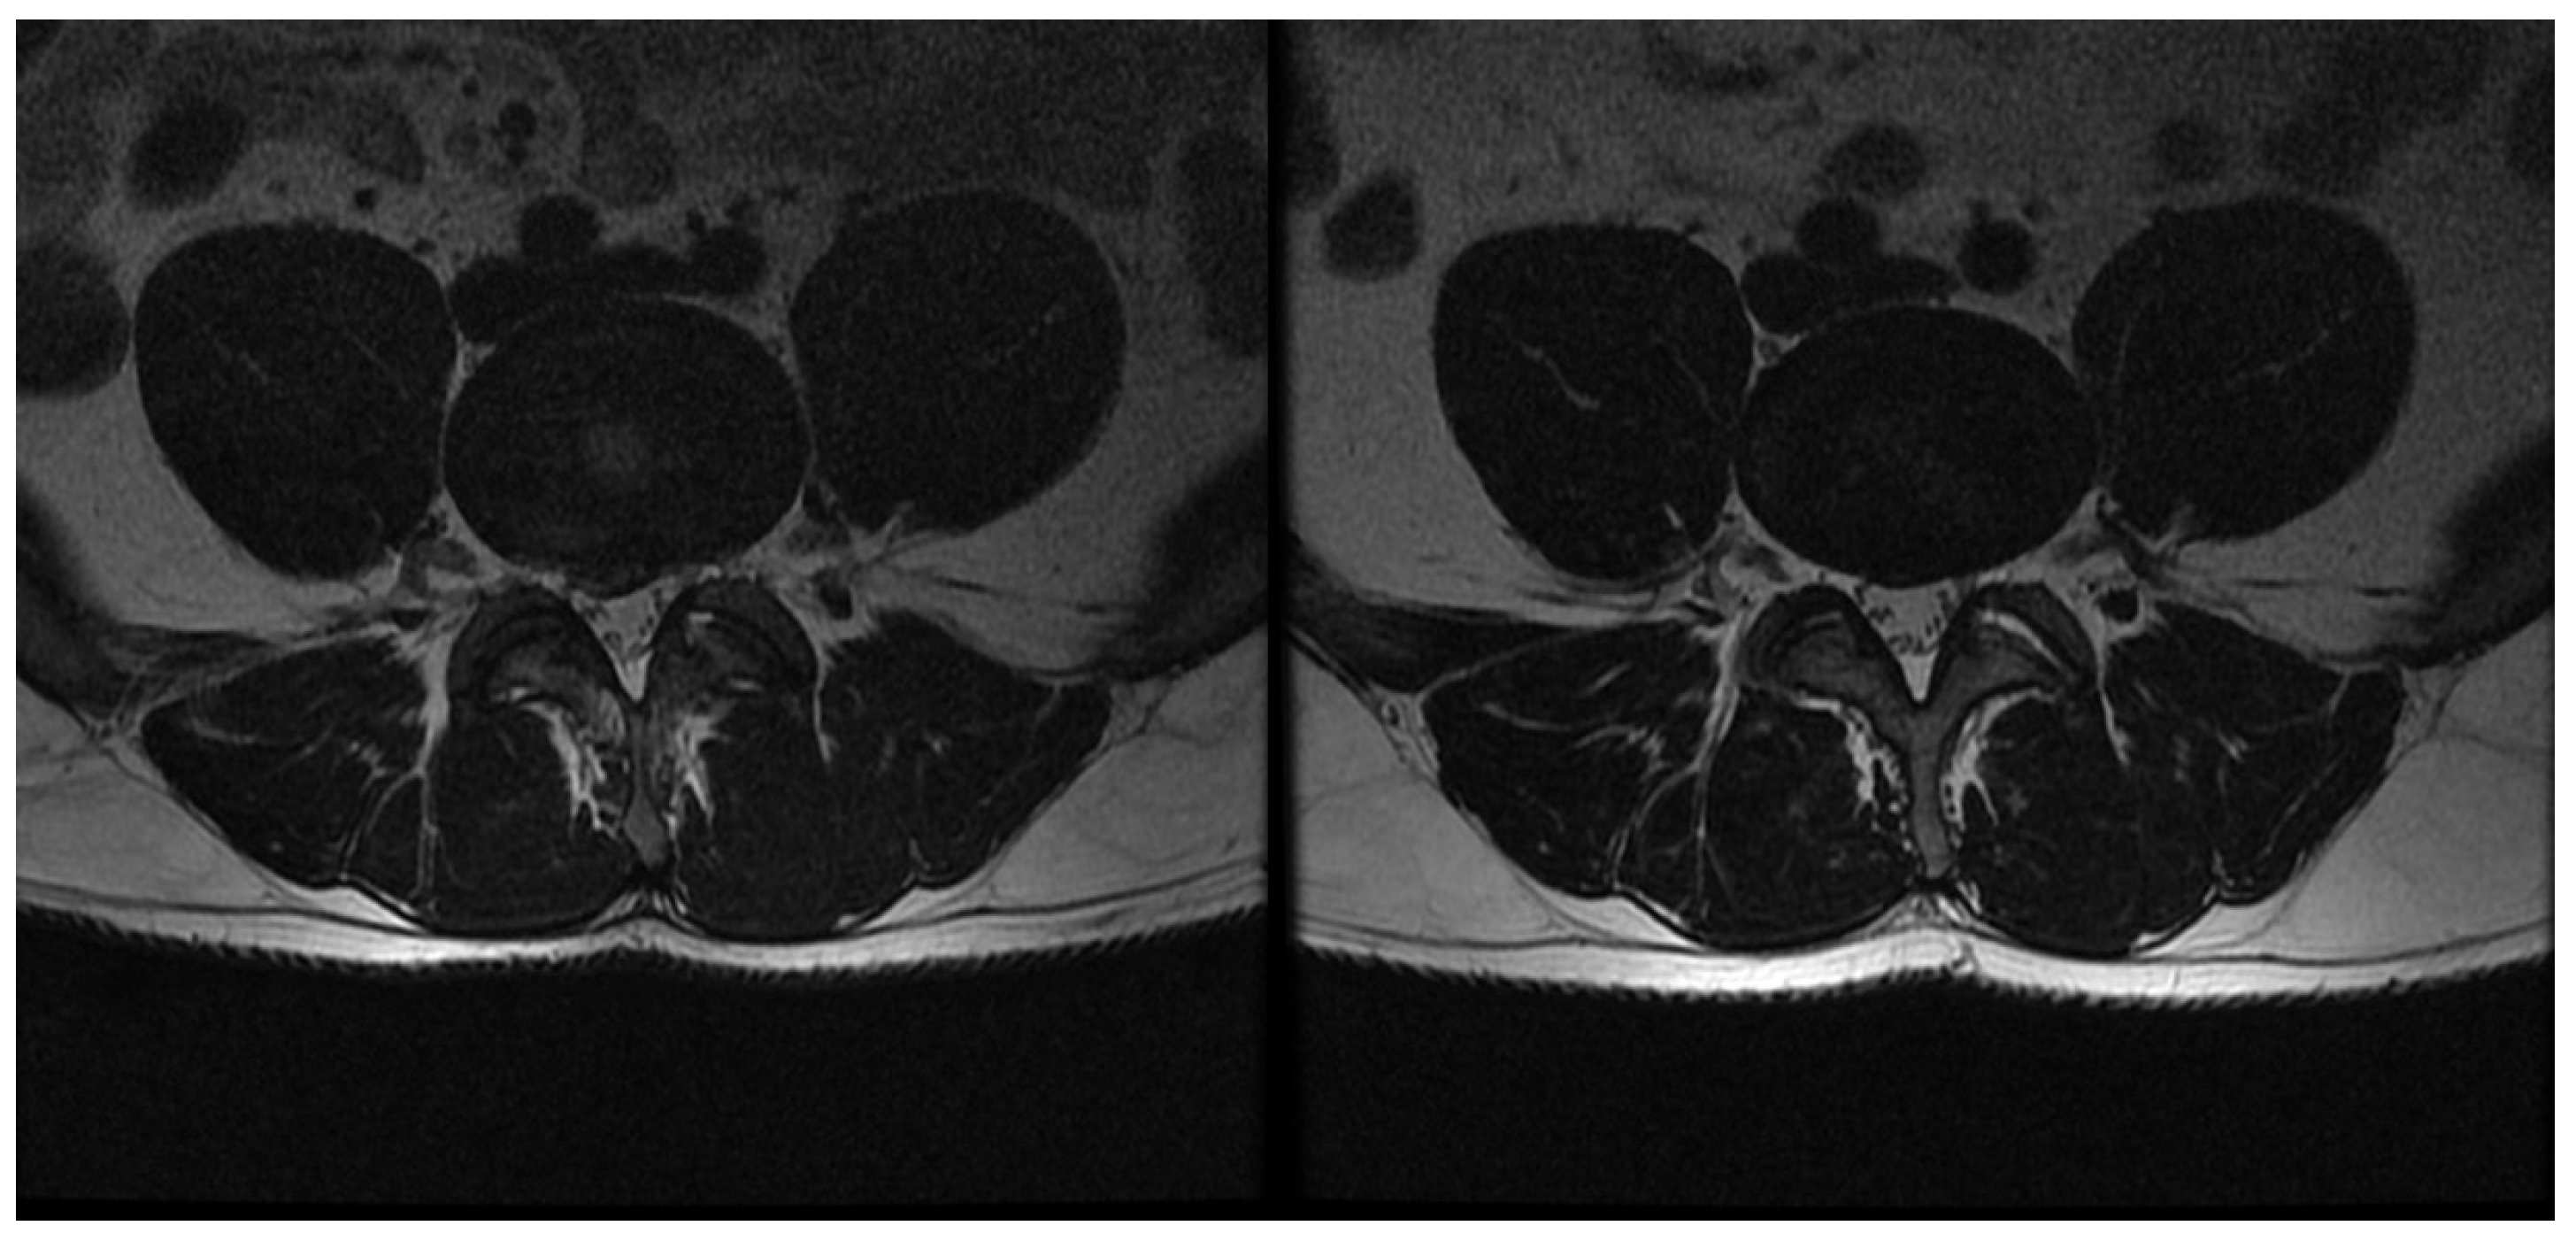

2.2. Procedure